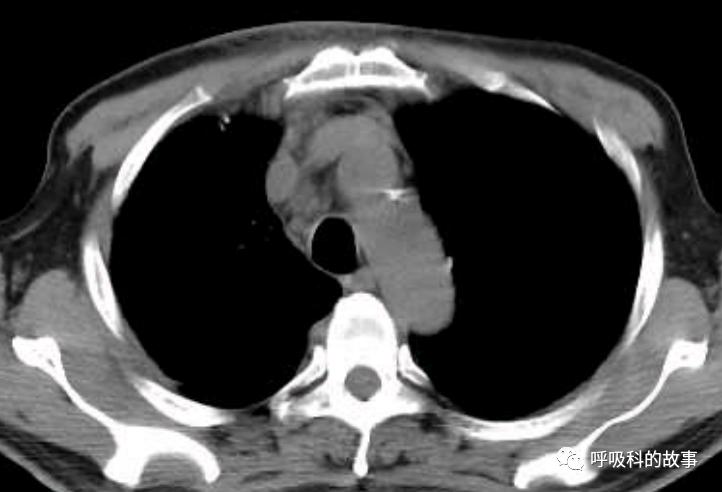

当时我们也曾经考虑给病人做淋巴结活检,但再次遭到患者的拒绝,由于患者体温正常,症状好转,我们也没有坚持。经过了两个多月的伏立康唑治疗,肺部影像基本吸收。

纵隔淋巴结也明显缩小了